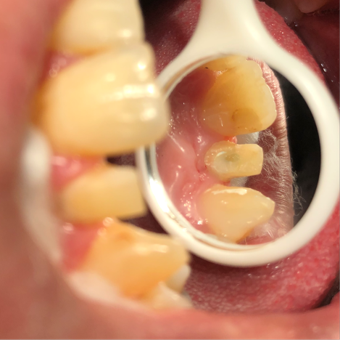

Root canal obturation

1/6/2025,post placement,tooth preparation,impression taking